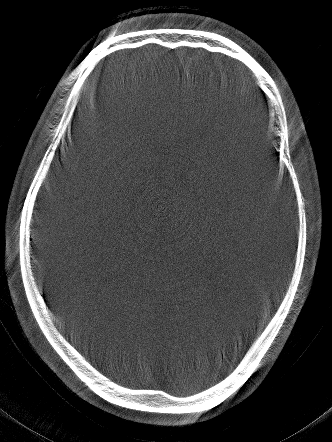

Figure 1: Network estimated RPE and different reconstructions, all revealing a RPE of 0.34absent0.34\approx 0.34 mm.

Figure 3 compares the proposed network-based IQM with the entropy-based IQM. The optimization process is identically for both metrics. In an inverse crime scenario both methods can restore the original image quality, however, in a more realistic setting the image entropy is stuck in a local minimum, whereas the network is able to lead the optimization to a nearby motion-free solution.

Ground Truth (Gt) and Motion Affected Inverse Crime Compensation Clinical Setting (Entropy and Proposed)

Figure 3: Reconstructions of the test patient using [500-2000] HU window. In the inverse crime scenario, the SSIM to the Gt is 0.840.840.84 (Ent/Gt) and 0.950.950.95 (Pro/Gt), respectively for the entropy (Ent) and proposed (Pro) measure. For the more realistic setting (Clinical Setting) the SSIM is 0.650.650.65 (Ent/Gt) and 0.840.840.84 (Pro/Gt), respectively.